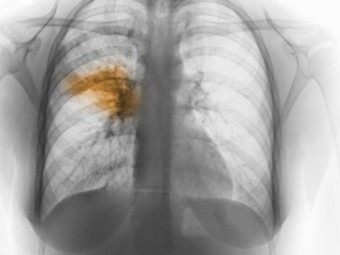

급성 폐렴은 폐 조직에 급성으로 염증이 발생하는 질환으로, 다양한 원인에 의해 발생하며 증상과 경과가 다양합니다. 이 글에서는 급성 폐렴의 증상, 원인, 치료 기간, 예방법에 대해 자세히 알아보겠습니다.

급성 폐렴의 증상은 원인 병원체와 환자의 상태에 따라 다를 수 있지만, 일반적으로 다음과 같은 증상이 나타납니다.

기침과 가래 : 기침은 폐렴의 대표적인 증상으로, 초기에는 마른기침으로 시작하여 점차 가래가 동반될 수 있습니다. 가래는 노란색 또는 녹색을 띠며, 때로는 피가 섞이기도 합니다.

발열과 오한 : 갑작스러운 고열과 함께 오한이 나타날 수 있습니다. 특히 38도 이상의 고열이 지속되면 폐렴을 의심해볼 수 있습니다.

흉통 : 깊은 숨을 들이쉴 때나 기침할 때 가슴 부위에 통증을 느낄 수 있습니다. 이는 폐를 둘러싼 늑막에 염증이 생겨 발생하는 증상입니다.

호흡곤란 : 호흡 시 숨이 차거나 곤란함을 느낄 수 있으며, 이는 폐의 염증으로 인해 산소 교환이 원활하지 않기 때문입니다.